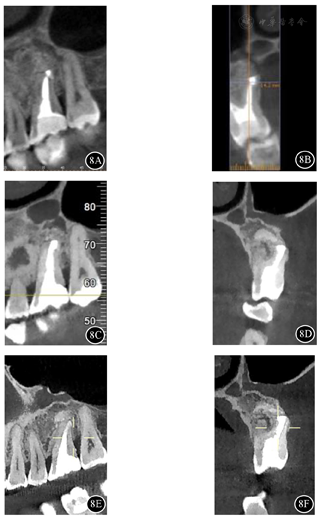

根尖片示26根尖区椭圆形低密度影。CBCT示26根尖区至左侧上颌窦底壁见不规则骨质缺损,缺损边缘见硬化,缺损区偏远中腭侧见一类椭圆形低密度影,边缘硬化,范围约13 mm×10 mm×8 mm,与骨缺损区相通;26见4根管,MB2内未见明显根管充填物影,根管钙化。诊断:26根尖囊肿。

面照;B:26颊面照影像学检查:根尖片示26根尖区椭圆形低密度影(图2)。锥形束CT(cone beam computed tomography,CBCT)示26根尖区至左侧上颌窦底壁见不规则骨质缺损,缺损边缘可见硬化。缺损区偏远中腭侧见一类椭圆形低密度影,边缘硬化,范围约13 mm×10 mm×8mm,与骨缺损区相通。26见4根管,MB(近颊根管)、DB(远颊根管)、P(腭根管)根管内见充填物影,MB2(近颊根第二根管)内未见明显根管充填物影,根管钙化(图3)。

术后2年CBCT示:26根尖部分切除,形态平钝,根管倒充填致密;根尖区骨密度较术前明显增加,但其上方至左侧上颌窦底壁以及颊侧骨皮质仍见缺损(图8A、图8B)。术后4年与术后5年CBCT影像表现基本同术后2年(图8C,图8D,图8E,图8F)。

26根尖区骨密度较术前明显增加,但根尖区颊侧骨皮质连续性部分中断,根据Penn影像学分类属于有限愈合。一般认为,无临床症状,并且影像学分类为完全愈合或有限愈合者,可视为成功。故本病例最终评价为成功。其上方至左侧上颌窦底壁存在骨质缺损,考虑为左上颌窦炎行左上颌窦根治术的术后表现。